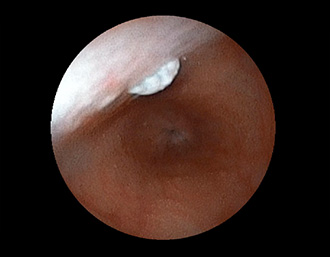

症例1:胃潰瘍(37才、男性)

①胃潰瘍(Stage A1)

健診:胃レントゲン検査で、胃角部ニッシェを指摘され当院受診。

胃角部小弯に、深くて大きな、大きさ約10mmの胃潰瘍(stage 1)があり、潰瘍底は一部白苔はみ出しを認める。エソメプラゾールマグネシウム水和物投薬で治療開始しました。

通常画像